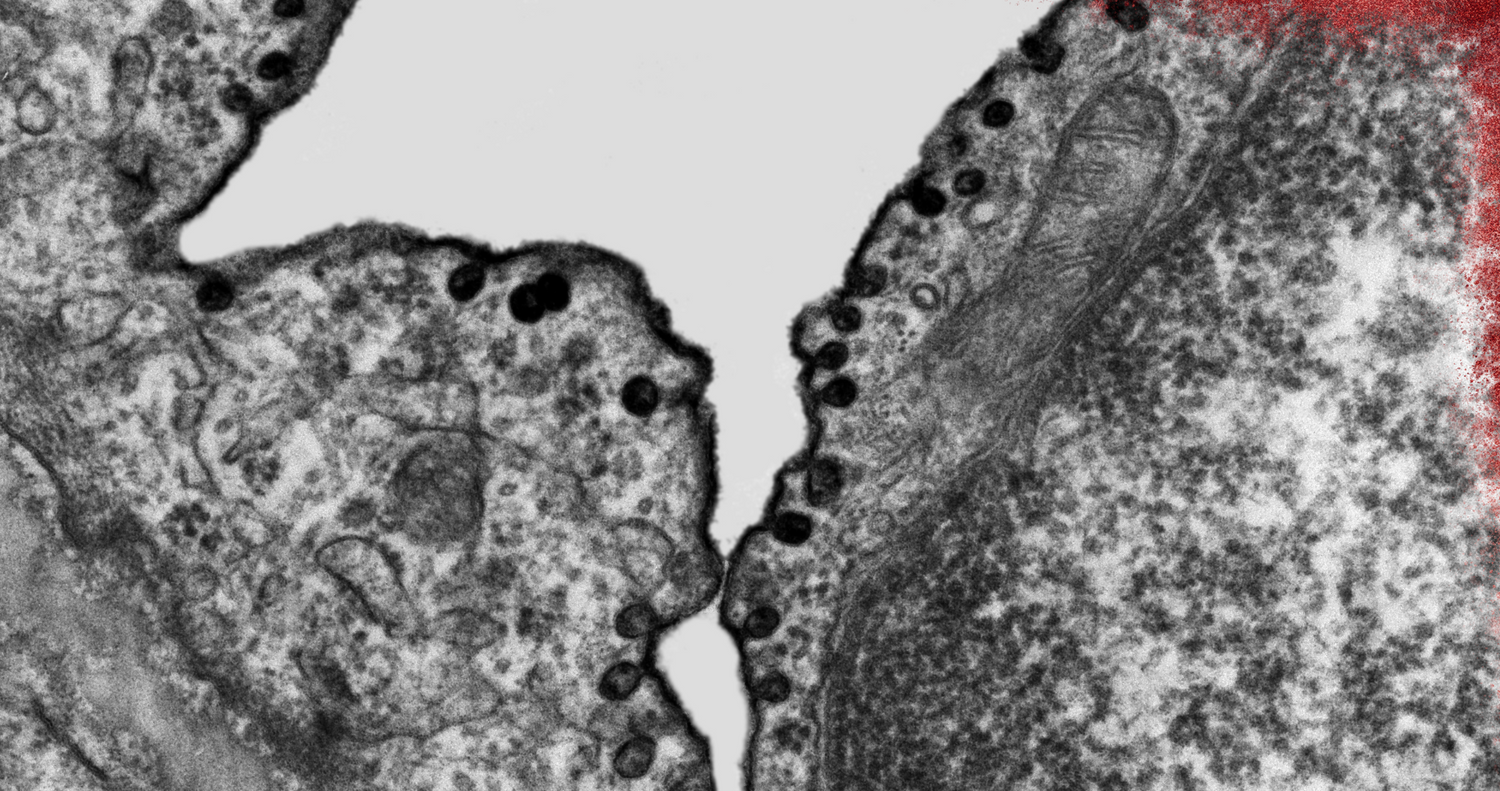

Endothelial cells are small but metabolically active. They regulate vascular tone through endothelial nitric oxide synthase, help control platelet stickiness, and coordinate immune traffic. Mitochondria in these cells generate ATP and act as redox hubs. When mitochondria are inefficient, reactive oxygen species rise and quench nitric oxide, which reduces vasodilation and raises vascular stiffness. Improving mitochondrial quality therefore supports two upstream goals for circulation. Preserve nitric oxide signaling and lower oxidative friction at the vessel wall.

Urolithin A promotes mitophagy. Cells tag dysfunctional mitochondria, recycle their components, and maintain a cleaner pool that produces ATP with fewer reactive byproducts. In endothelial biology, that tilt can protect nitric oxide from oxidative quenching and reduce inflammatory signaling that otherwise triggers adhesion molecules on the vessel surface. Preclinical work in vascular and metabolic stress models reports that Urolithin A reduces markers of oxidative stress, lowers pro-inflammatory cytokines such as TNF-α and IL-6, and supports mitochondrial respiration in cardiovascular tissues. The net effect is a cellular environment that is friendlier to nitric oxide and smoother blood flow.